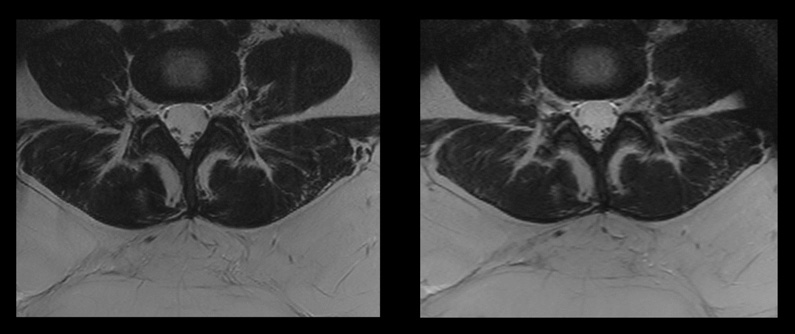

Confronto tra due sequenze spinali, con e senza Compressed SENSE.

Immagine a sinistra: scansione convenzionale, con livello di SAR di 2,5 W/kg e tempo di scansione di 7,33 minuti.

Immagine a destra: scansione mediante Compressed SENSE, con livello di SAR di 1,9 W/kg e tempo di scansione di 3,21 minuti.